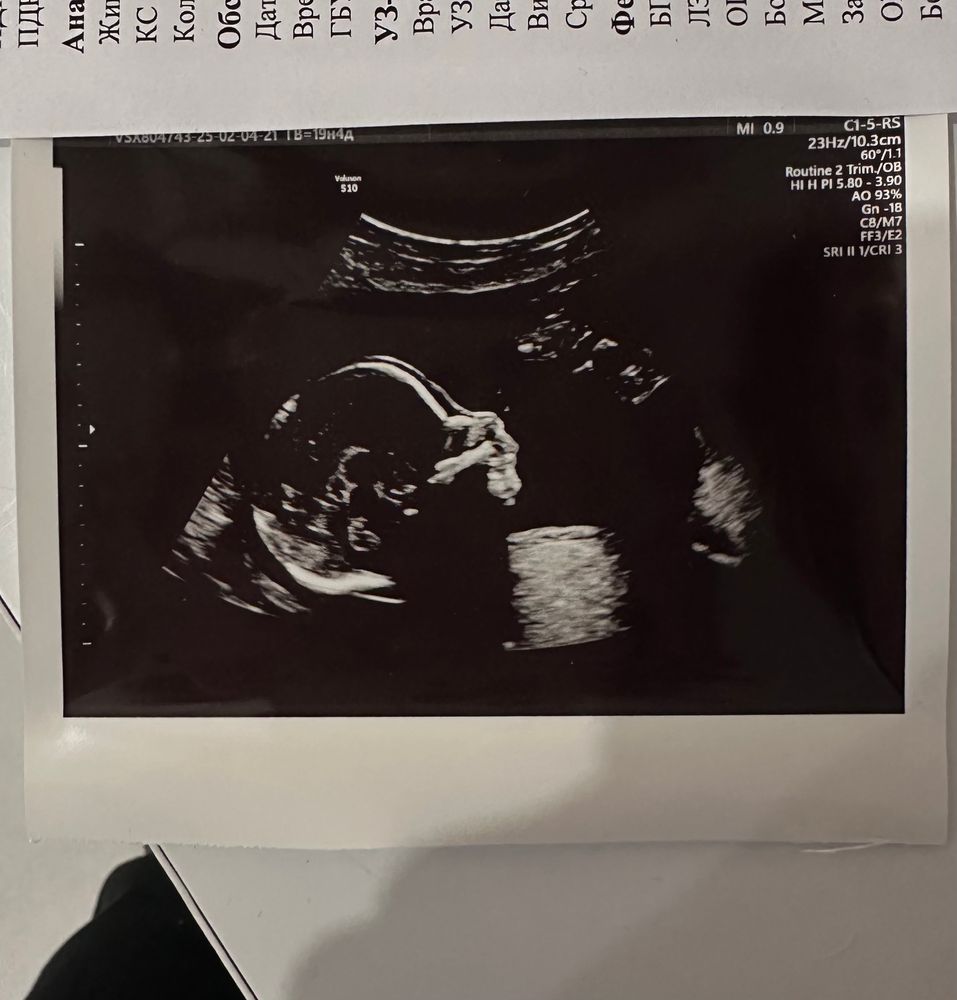

Экватор. Мои 20 неделек.

Изображение

Прошла я второй скрининг, все хорошо, наш мальчик растет как надо, плацента поднимается, но шейка все так же предательски коротковата (30мм). Набрала уже на данный мом